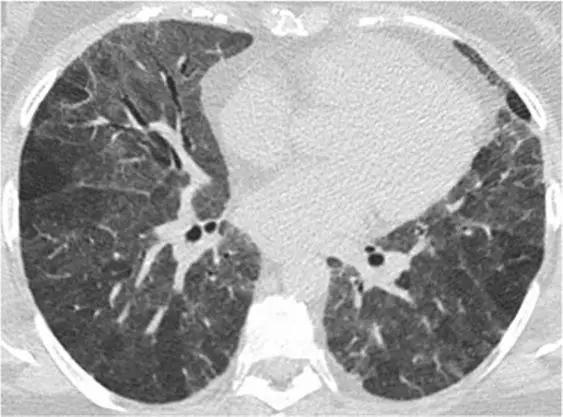

5、磨玻璃影-网状影混杂模式

有时,在肺部同一区域中可能同时存在磨玻璃样影和网状影共存,这种组合几乎等同于不可逆的纤维化。典型疾病:是非特异性间质性肺炎(NSIP)。表现为磨玻璃影改变为主、轻度网状改变。鉴别疾病:硬皮病、特发性肺纤维化(IPF)和脱屑性间质性肺炎(DIP)。

硬皮病的肺部侵袭类似于NSIP,因为它是最常见的组织学类型的纤维化。有利于硬皮病的主要发现是食管扩张和肺动脉扩张。

*硬皮病。下叶水平的HRCT表现为混合的“磨玻璃样和网状样”,其特征是磨玻璃样改变和牵引性支气管扩张。请注意5 mm胸膜下不受累,这是硬皮病最常见的组织学类型NSIP的特征相关性肺纤维化。

特发性肺纤维化(IPF)有时可能与NSIP难以区分,HRCT在区分IPF和NSIP方面的特异性范围为63%至70%。有利于IPF的鉴别诊断是呈现显著的网状蜂窝样改变,少许毛玻璃改变。

*IPF HRCT在肺底水平上表现出混合的“磨玻璃样和网状图案”,其特征是磨玻璃样改变的区域内可见牵引性支气管扩张和支气管扩张。少许蜂窝样改变。